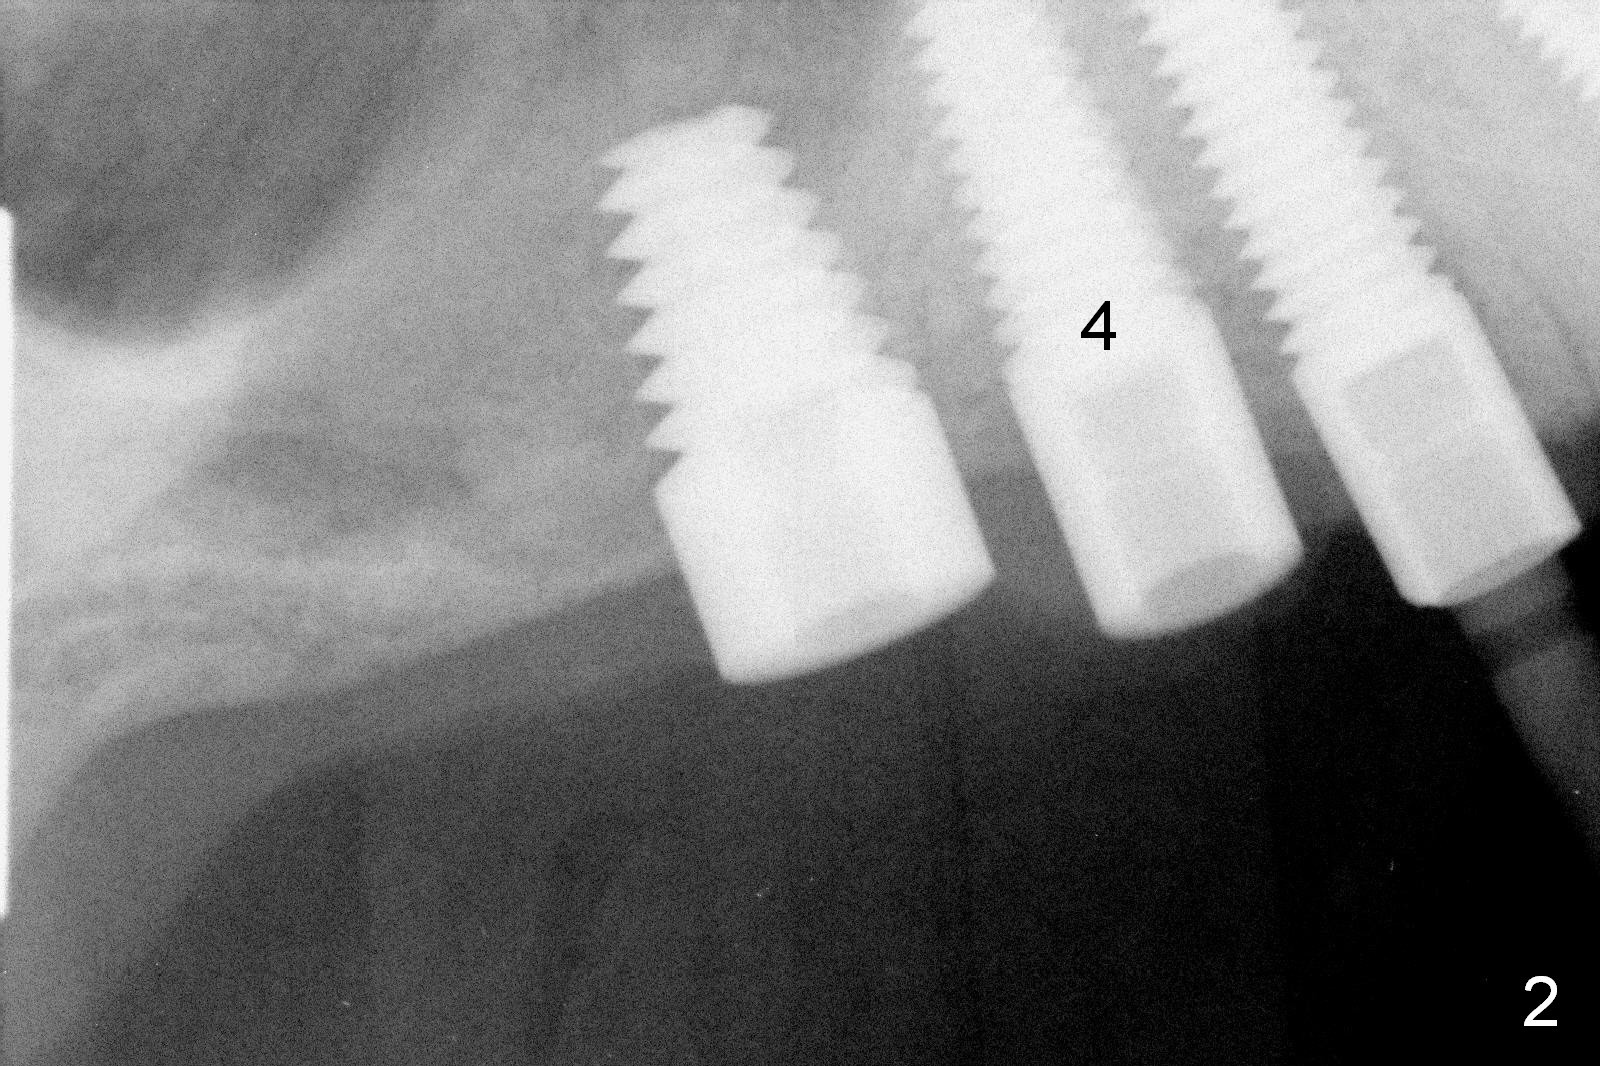

A 57-year-old man has history of chronic periodontitis.  The tooth #3 had been lost and the teeth #4 and 5 were extracted 5 years ago.  CT taken post extraction shows a palatal defect at #4.  The implants at #3 and 5 were placed a month prior to that at #4 (Fig.2 (4.5x14 mm); 2 years ago).  A splinted provisional was fabricated between #3 and 5, half month post #4 implant placement.  Final restorations were cemented 4 months later.